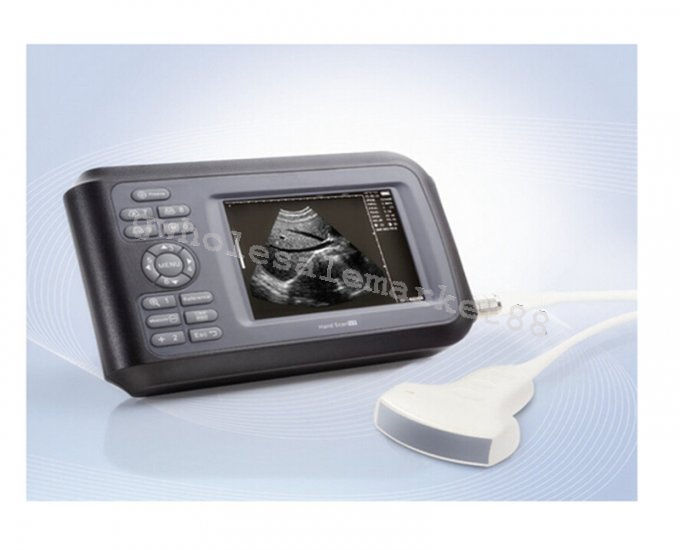

The laptop ultrasound scanner is designed for versatility and ease of use. It features both Convex and Transvaginal probes, allowing for comprehensive examinations in various settings. This scanner ensures high precision in imaging, giving healthcare providers the ability to make accurate diagnoses quickly. Because of its ergonomic design, it's easy for practitioners to operate, so they can achieve clear images with minimal effort.

One of the standout features of this laptop ultrasound scanner is its portability. Weighing less than conventional ultrasound machines, it allows healthcare professionals to bring it right to the patient’s side. Plus, the user-friendly interface simplifies the operation, making it suitable for medical staff of all experience levels. Also, the compact size ensures that it fits easily into tighter spaces, such as small clinics or in-home care environments.